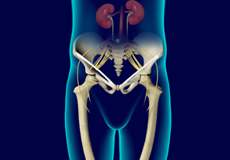

Septic Arthritis

Septic arthritis also called as infectious arthritis, is characterized by joint inflammation due to a bacterial or fungal infection that usually affects the large joints of the body such as knee or hip.

Osteomyelitis

Bone infection or osteomyelitis is a serious medical condition that needs immediate medical attention. Infection may occur due to an open fracture or surgery or infection in one area of the body may spread to the bone via the bloodstream.